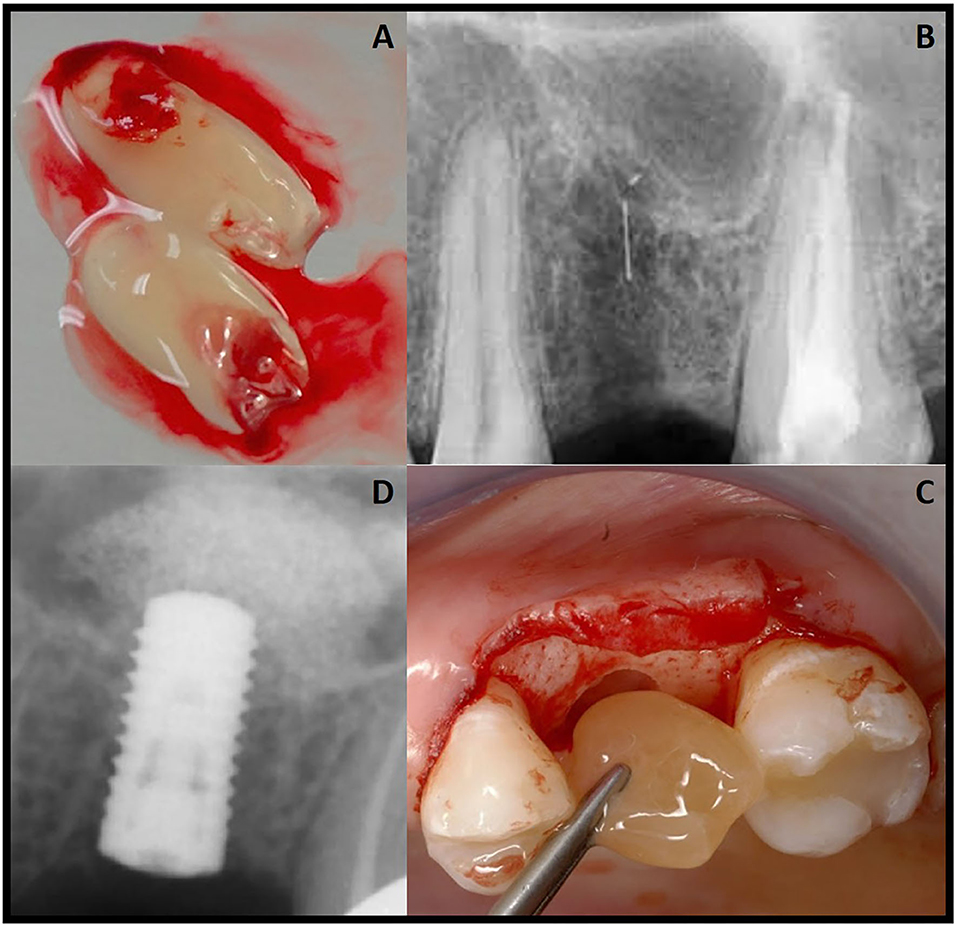

자가치아뼈이식 과정

발치부터 이식까지 안전하고 체계적인 과정

발치 및 수집

치아를 조심스럽게 발치하여 손상 없이 수집

세척 및 소독

특수 용액으로 치아를 철저히 세척하고 소독

분쇄 및 처리

이식에 적합한 크기로 분쇄하여 가공

이식재 적용

필요한 부위에 가공된 자가치아 이식재 적용

치유 및 재생

3-6개월간 새로운 뼈 조직으로 재생

발치와 보존술

발치 후 자가칙아로 발칙와를 보존하여 임플란트 준비

주요 장점

- 발치와 형태 보존

- 골흡수 방지

- 임플란트 성공률 향상